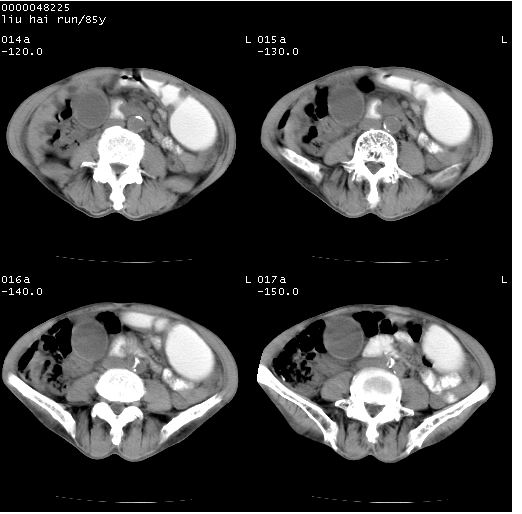

标题: CT13403:M,85Y。胆系低位梗阻。胰头占位? [打印本页]

标题: CT13403:M,85Y。胆系低位梗阻。胰头占位?

彩超示胰头实质欠均匀,胰管扩张。

有“双管征”,胆总管胰头段突然中断,考虑为胰头癌。

影像表现:壶腹部扩张胆管呈截断样改变,肝内外胆管重度扩张,胆囊增大,胰管亦明显扩张,呈不规则患珠样,胰体尾部略有萎缩,增强扫描后壶腹部低密度影轻度强化,与钩突分界不清。

ct诊断:胆管癌。鉴别诊断:胰腺癌,胰腺癌为少血供肿瘤,增强后强化不明显,静脉期及延时后与正常胰腺分界清晰。

胆总管下端突然截断,胰腺萎缩,胰管扩张,肝内外胆管扩张,考虑胆总管下端癌可能性大。不除外胰腺钩突占位。

1)胆系低位梗阻(肝内外胆管扩张、胰管扩张、胆囊增大);考虑为:胰头癌可能性大,不排除胆总管下端癌。2)双肾多发囊肿。